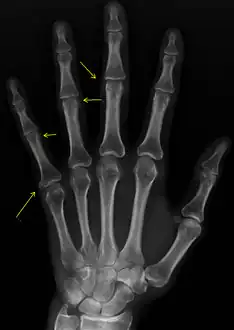

X-rays showing calcinosis in a woman with CREST syndrome

X-ray of subtle calcifications in CREST syndrome